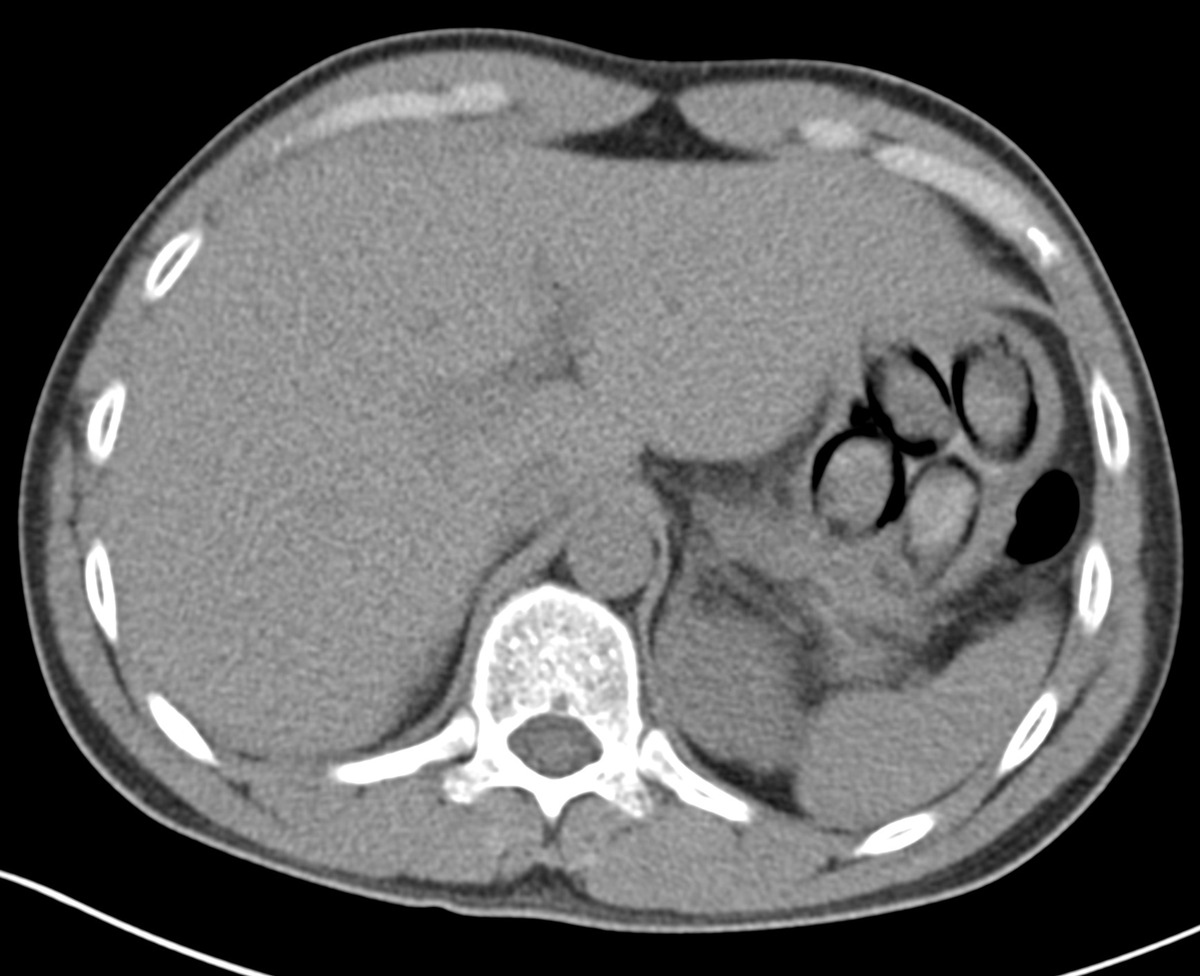

Daar toonde een röntgenonderzoek meerdere pakketjes in zijn maag. Onder toezicht scheidde de man uiteindelijk zeven zogenoemde bodypacks uit, goed voor meer dan 100 gram cocaïne.